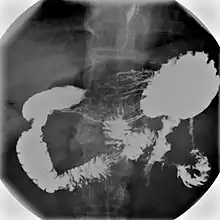

An upper gastrointestinal series, also called a barium swallow, barium study, or barium meal, is a series of radiographs used to examine the gastrointestinal tract for abnormalities. A contrast medium, usually a radiocontrast agent such as barium sulfate mixed with water, is ingested or instilled into the gastrointestinal tract, and X-rays are used to create radiographs of the regions of interest. The barium enhances the visibility of the relevant parts of the gastrointestinal tract by coating the inside wall of the tract and appearing white on the film. This in combination with other plain radiographs allows for the imaging of parts of the upper gastrointestinal tract such as the pharynx, larynx, esophagus, stomach, and small intestine such that the inside wall lining, size, shape, contour, and patency are visible to the examiner. With fluoroscopy, it is also possible to visualize the functional movement of examined organs such as swallowing, peristalsis, or sphincter closure. Depending on the organs to be examined, barium radiographs can be classified into "barium swallow", "barium meal", "barium follow-through", and "enteroclysis" ("small bowel enema"). To further enhance the quality of images, air or gas is sometimes introduced into the gastrointestinal tract in addition to barium, and this procedure is called double-contrast imaging. In this case the gas is referred to as the negative contrast medium. Traditionally the images produced with barium contrast are made with plain-film radiography, but computed tomography is also used in combination with barium contrast, in which case the procedure is called "CT enterography".[1]

Various types of barium X-ray examinations are used to examine different parts of the gastrointestinal tract. These include barium swallow, barium meal, barium follow-through, and barium enema.[2] The barium swallow, barium meal, and barium follow-through are together also called an upper gastrointestinal series (or study), whereas the barium enema is called a lower gastrointestinal series (or study).[3] In upper gastrointestinal series examinations, the barium sulfate is mixed with water and swallowed orally, whereas in the lower gastrointestinal series (barium enema), the barium contrast agent is administered as an enema through a small tube inserted into the rectum.[2]

- Barium meal examinations are used to study the lower esophagus, stomach and duodenum.[2]

Right anterior oblique (RAO) view is used to demonstrate antrum and greater curve of stomach. Supine position is to demonstrate antrum and body of stomach. Left anterior oblique (LAO) view is used to see the lesser curve of stomach en face. This position is also used to check for gastroesophageal reflux when patient is asked to cough or swallow (water siphon test). Left lateral tilted with head up 45 degrees is used to demonstrate the fundus of the stomach.[13] To demonstrate the duodenal loop, the subject can lie down in prone position on a compression pad to prevent excessive barium flowing into the duodenal loop. Anterior view of duodenal loop can be seen at RAO position.[13] Duodenal cap can be visualised by taking images when subject lie down in prone position, RAO, supine, and then LAO positions or it can be seen on erect position with RAO and steep LAO views.[13] Total mucosal coating of the stomach is done by asking the subject to roll to the right side into a complete circle until RAO position. Arae gastriae in the antrum (fine reticular network of grooves) is visible if good coating is achieved.[13]